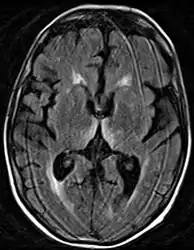

-

Axial MRI FLAIR image showing hyperintense signal in the mesial dorsal thalami, a common finding in Wernicke encephalopathy. This patient was nearly in coma when IV thiamine was started, he responded moderately well but was left with some Korsakoff type deficits. -